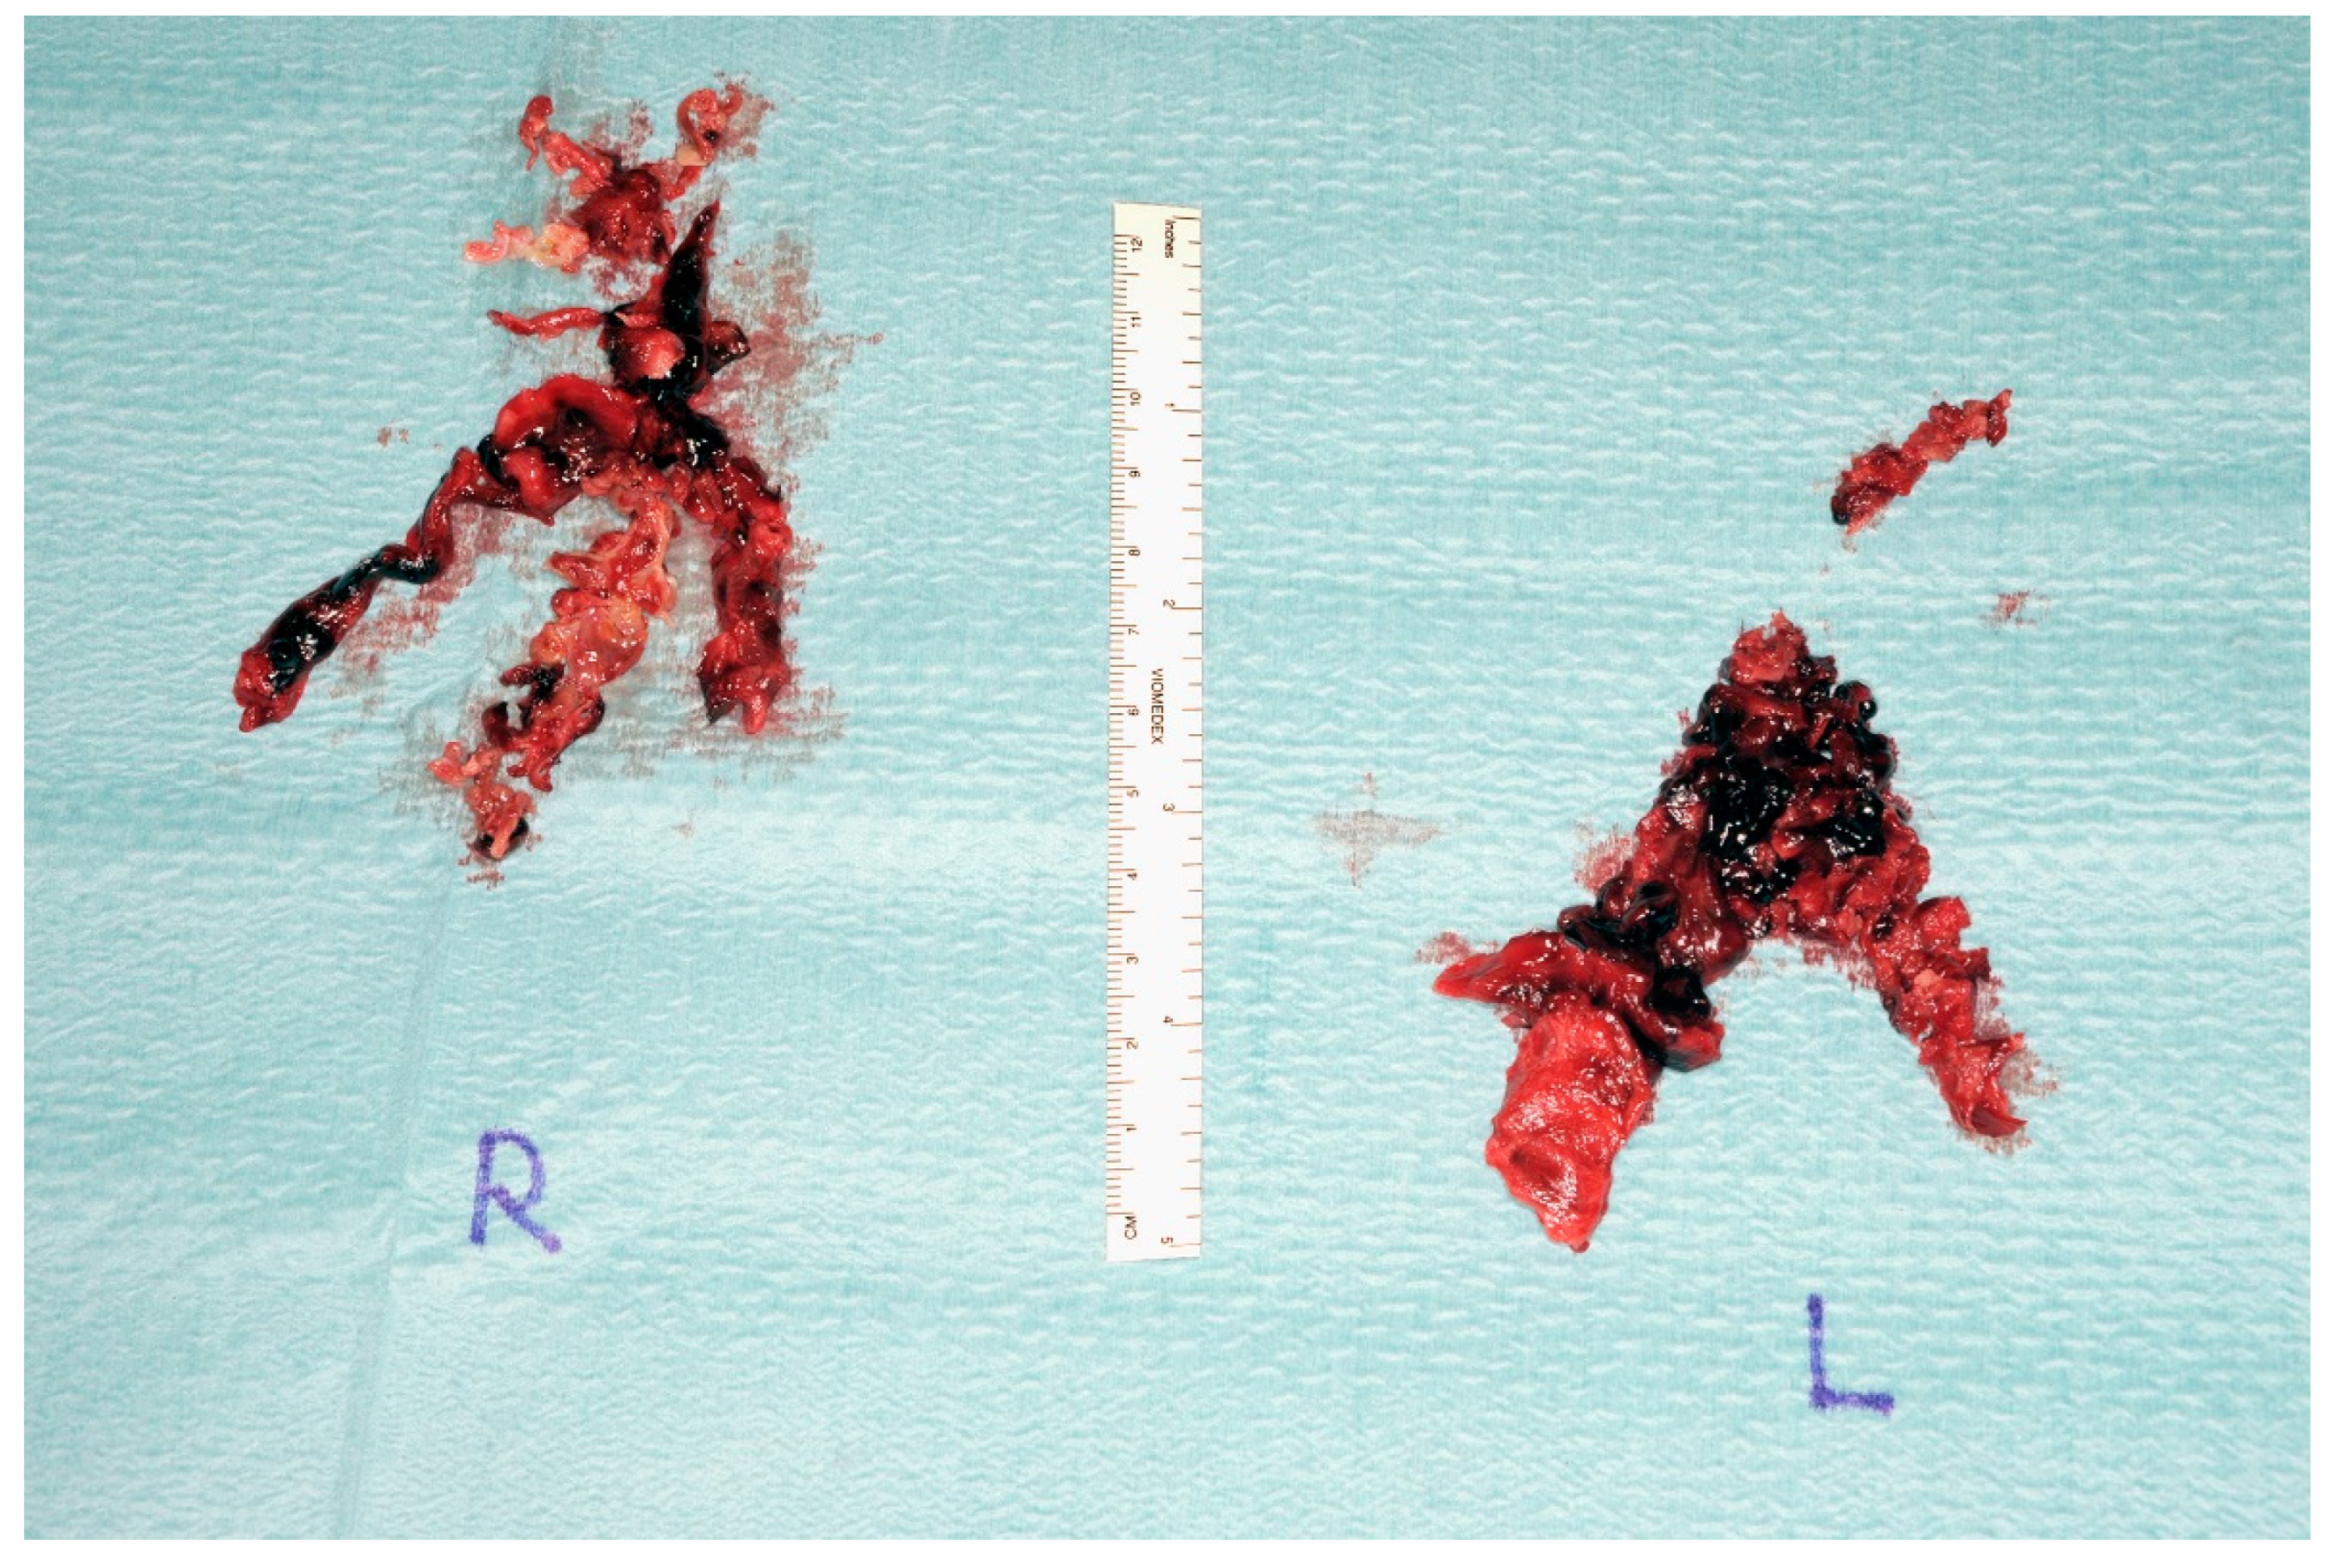

3.3. Imaging

3.4. Computed Tomography Pulmonary Angiography (CTPA)